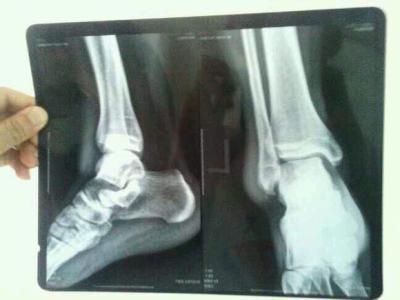

图片来源于网络

撕脱性骨折多发生于脚踝,膝盖、肘关节等位置,而脚踝在运动时或者遭遇交通事故的时候相对是比较容易受伤的,在众多的骨折中,运动中或者交通事故中足踝处最常发生撕脱性骨折。